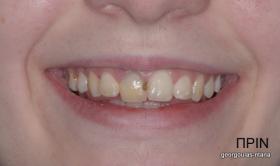

ΑΠΟΚΑΤΑΣΤΑΣΗ ΑΝΩ ΚΕΝΤΡΙΚΟΥ ΤΟΜΕΑ ΜΕ ΜΟΝΗΡΕΣ ΕΜΦΥΤΕΥΜΑ

Η κοπέλα αυτή ήρθε στο ιατρείο με κάταγμα στον δεξιό άνω κεντρικό τομέα. Το δόντι είχε απονευρωθεί στο παρελθόν και είχε αποκατασταθεί με βιδωτό άξονα κ ανασύσταση με ρητίνη και το αισθητικό αποτέλεσμα ήταν φτωχό. Η ασθενής ήθελε να είναι καλυμμένη αισθητικά για όσο χρονικό διάστημα θα διαρκούσε η θεραπεία. Πραγματοποιήθηκε τομογραφία κωνικής δέσμης (CBCT) στην περιοχή και αποφασίστηκε να γίνει εξαγωγή του δοντιού, διατήρηση του όγκου του φατνίου και 3 μήνες μετά τοποθέτηση εμφυτεύματος με ταυτόχρονη χρήση μοσχευμάτων σκληρών κ μαλακών ιστών  για βέλτιστο αισθητικό αποτέλεσμα. Το εμφύτευμα αποκαταστάθηκε με υβριδικό κολόβωμα από διπυριτικό λίθιο και ολοκεραμική στεφάνη από διπυριτικό λίθιο (Emax). Καθ’ όλη τη διάρκεια της θεραπείας, η ασθενής ήταν καλυμμένη αισθητικά με γέφυρα Meryland  συγκολλημένη στα δύο διπλανά δόντια. Μετά την οστεοενσώματωση του εμφυτεύματος και πριν την τελική αποκατάσταση, τοποθετήθηκε στο εμφύτευμα προσωρινή εργασία με σκοπό τη βελτίωση των ούλων.